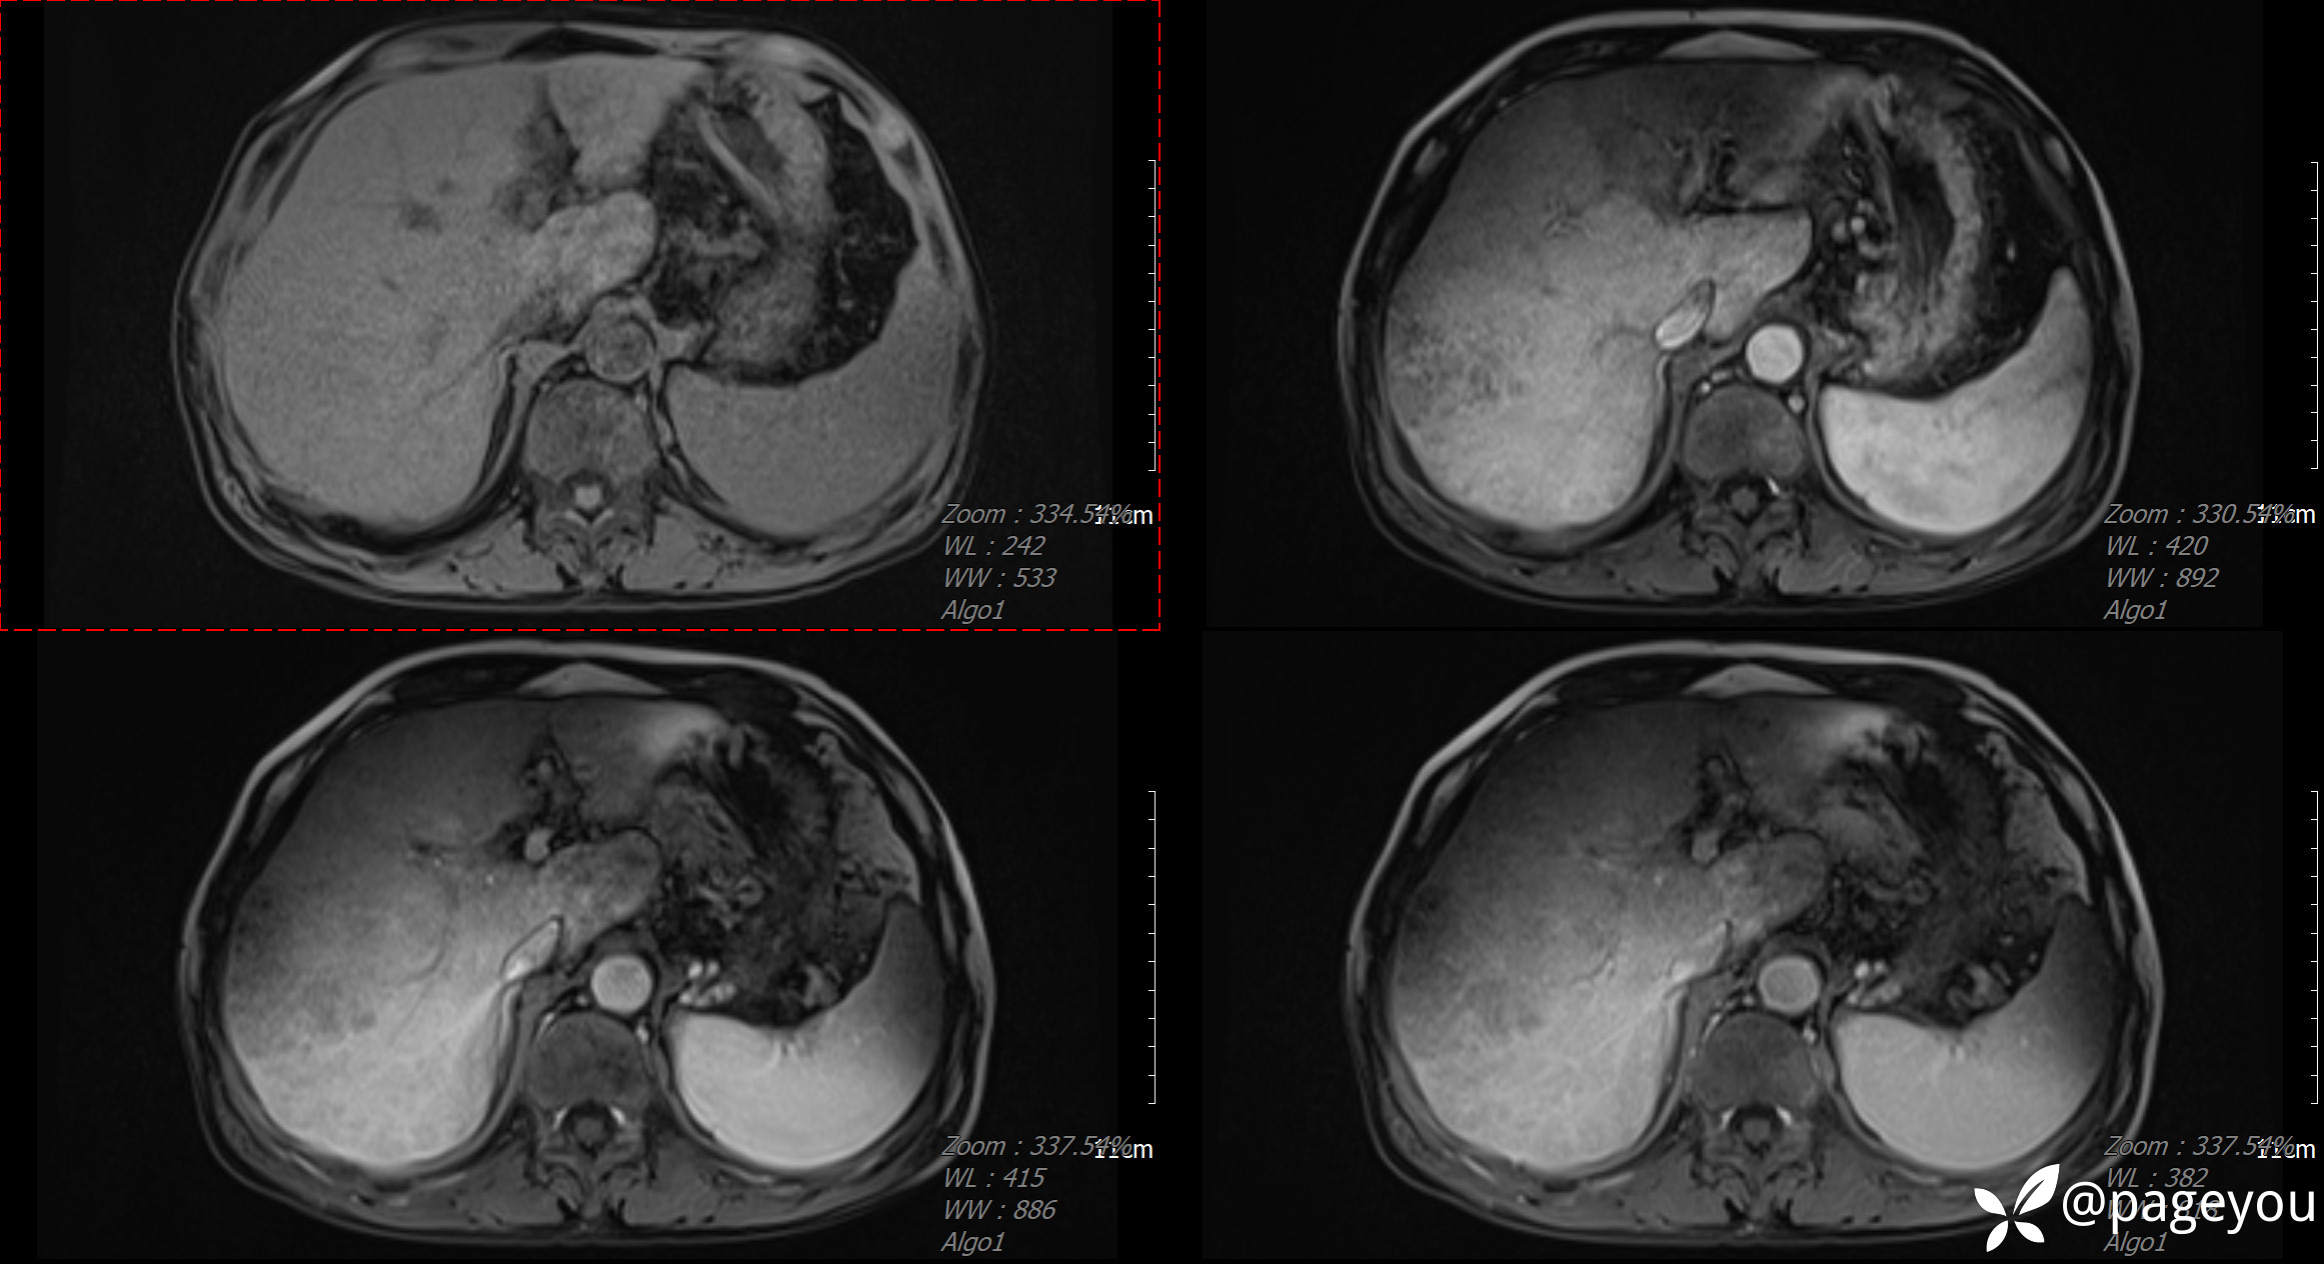

CT检查:

MRI检查: